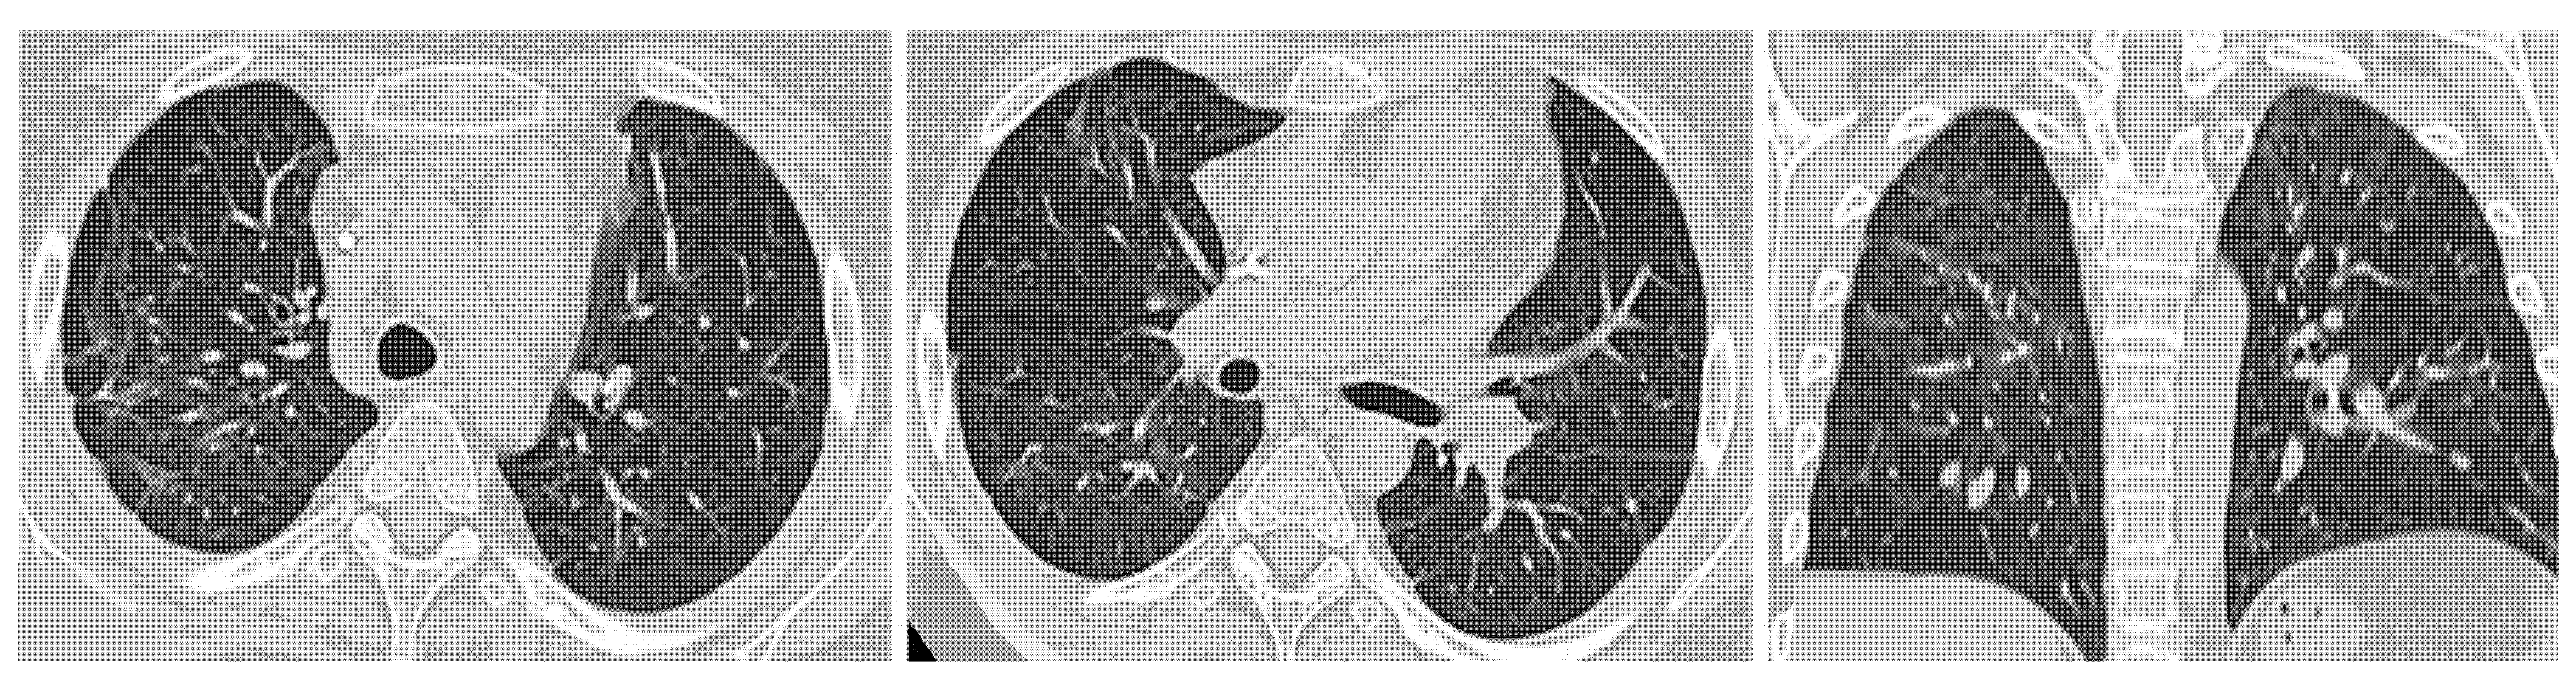

4.2.1. HRCT Findings of Patients with Anti-ARS Abs

- Waseda, Y.; Johkoh, T.; Egashira, R.; Sumikawa, H.; Saeki, K.; Watanabe, S.; Matsunuma, R.; Takato, H.; Ichikawa, Y.; Hamaguchi, Y.; et al. Antisynthetase syndrome: Pulmonary computed tomography findings of adult patients with antibodies to aminoacyl-tRNA synthetases. Eur. J. Radiol. 2016, 85, 1421–1426. [Google Scholar] [CrossRef]

| Lesions | GGO, reticulations, consolidations | consolidations, GGOs | |

| Distribution | Homogeneous; lower lung lobes, along bronchovascular bundles and lung periphery; loss of volume of lower lobes | Patchy; peripheral lower lobes or along the bronchovascular bundles | |

| CT pattern | NSIP OP NSIP-OP UIP DAD-unclassifiable | 50% 20% 25% 10% +/− | 20% 50% 25% <5% ++ |